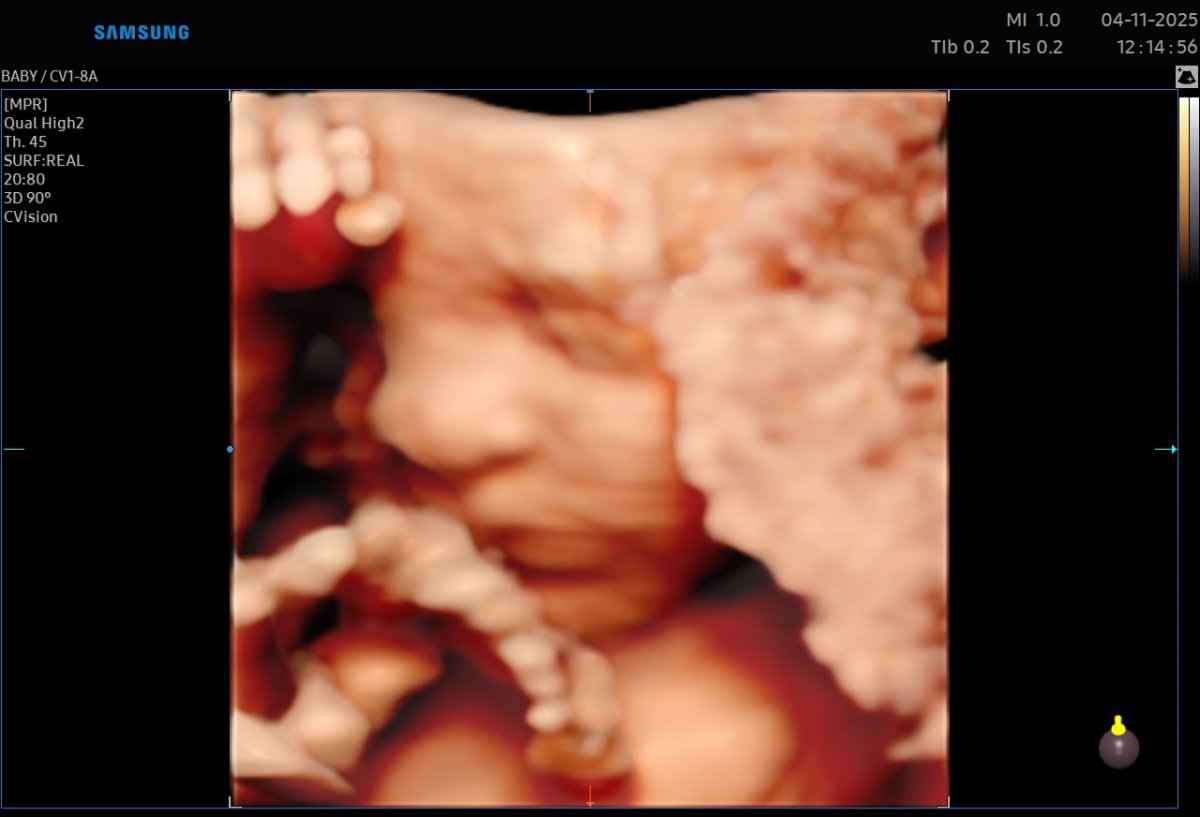

Gallerie de photos